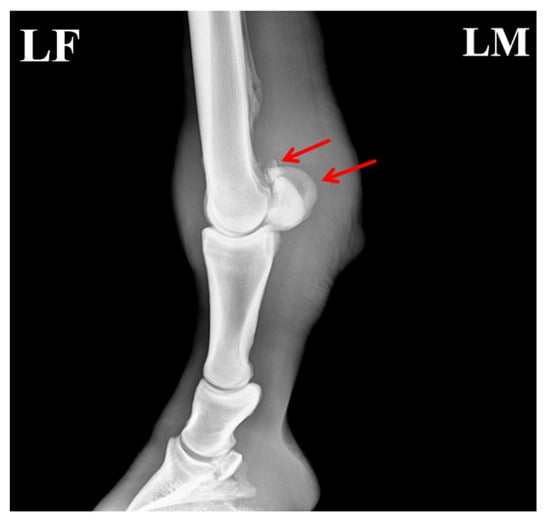

Radiographic evaluation was performed to assess the type of lesion and to determine whether flexor tendinitis was present. Images were taken of the left forelimb (LF) in lateromedial (LM) and dorsopalmar/anteroposterior (AP) projections. The radiographs showed a clear fracture line at the proximal apex of the left proximal sesamoid bone, with separation of the fracture margins and the presence of a small free bone fragment. The fragment had an irregular shape and was displaced away from the main sesamoid body. Local cortical continuity was disrupted, and the trabecular pattern appeared disorganized. An increase in soft-tissue density was also noted in the flexor tendon region, raising suspicion of concurrent flexor tendinitis (Figure 2).

Figure 2. Radiographic features of the affected horse with PSBF. (A) Fracture at the apex of the proximal sesamoid bone (red arrow: bone fragments; blue arrow: increased radiodensity in the flexor tendon region). (B) Fracture fragments of the proximal sesamoid bone. The arrows indicate the specific lesions.